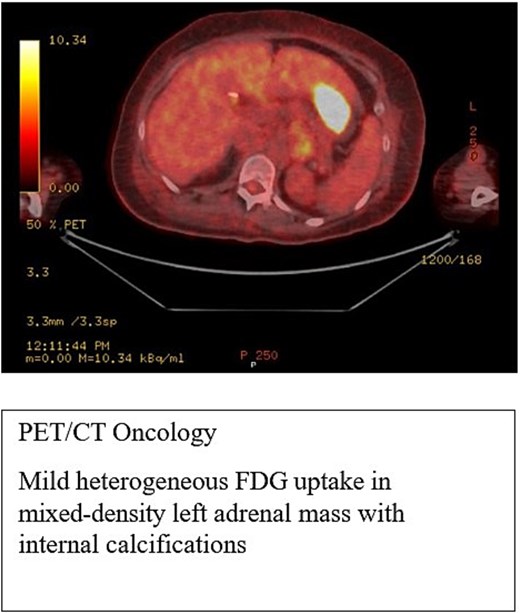

A PET/CT scan (Fig. 3) showed mild heterogeneous fluorodeoxyglucose (FDG) uptake in a mixed-density left adrenal mass with calcifications. The radiologist suspected a left adrenal mass, with differential diagnoses including pheochromocytoma or previous hemorrhage.

PET-CT scan showed heterogeneous FDG uptake in a mixed-density left adrenal mass with internal calcifications.